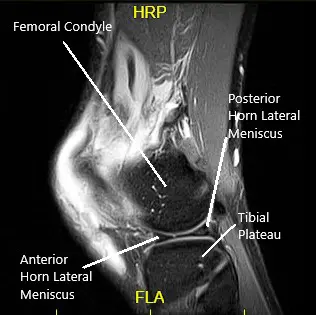

MRI suggested a complete rupture of the quadriceps tendon at the patellar attachment. The joint effusion communicates through the tendon defect with a prepatellar fluid collection. Low-grade intrasubstance tear at the origin of the ACL. Radial tear at the free edge of the lateral meniscal body.

MRI of the left knee in the sagittal and coronal view.